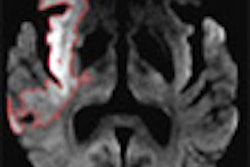

First, Stebbins pointed out that present MR sequences, such as T2 relaxation, has allowed for the pathological quantification of white matter. Processing techniques, such as semiautomated and fully automated processing, have also contributed to a greater understanding of this part by allowing clinicians to not only delineate individual neurological components (white matter, gray matter, cerebral spinal fluid), but also to compare these components among groups of patients.

One of the newer techniques that has already offered greater insight into white matter is magnetization transfer imaging (MTI), Stebbins said. MTI looks at the ratio between bound and unbound protons. An increase or decrease in this ratio is indicative of the integrity of myelin.

"MTI has been looked at in white-matter hyperintensities in asymptomatic elderly individuals, and has shown a decrease in these hyperintensities. In addition, it's been shown that there is a slight decline in the ratio in normal-appearing white matter with age," he said. "So as we grew older, the ratio declines slightly. This decline is accentuated in specific regions of the cerebrum, including the frontal lobes and the parietal-occipital regions."

DTI "allows us to detect 3D motion of hydrogen in the brain, both for magnitude and direction, and gives us a measure of anisotrophy, which is the shape of the diffusion," he stated. "It's the degree to which the diffusion differs in three dimensions." DTI offers insights into the white-matter differences between stroke patients with cognitive impairment and those without. It can be used to evaluate white-matter integrity in relation to psychomotor processing speed, Stebbins added.

"(With DTI), by looking at the coherence of the direction between neighboring voxels, one can begin to develop a description of the white-matter brain pathway in the brain," he explained.